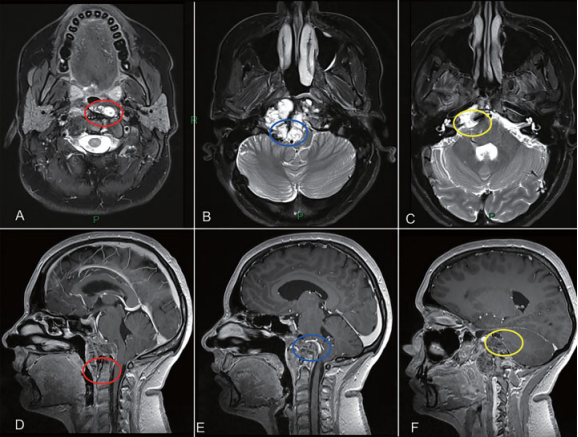

图2治疗策略。肿瘤的旁正中部分可以通过EEA切除。另一方面,periodontoid region(A和D为红色圆圈)、硬膜内肿瘤与后循环接触(B和E为蓝色圆圈)和先前乙状窦后入路的粘连(C和F为黄色圆圈),这些部位似乎更适合二期经颅手术。(A-C)MRI T2 WI。(B-D)MRI T1 WI Gd增强。